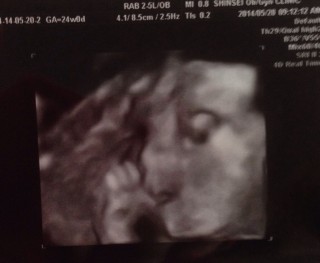

写真:24w0d:manaさん

7ヶ月最初の日に健診。中期スクリーニングでしたが、後ろ向きで爆睡してたベビさん。心臓の写真をもっと撮りたいけど、『ちょーど隠れてて見えにくいなぁ…』と先生。それでも時間かけて、大動脈や心臓の弁まで見てもらえました。600g.手足の骨もしっかり見えて安心です。